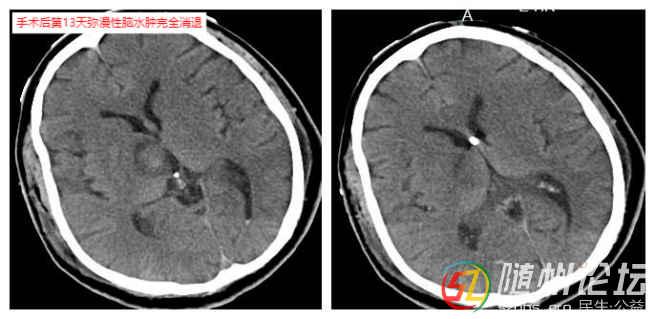

術(shù)后患者如預(yù)期出現(xiàn)彌漫性腦水腫,到術(shù)后第6天達到彌漫性腦水腫高峰,得益于冒著巨大風(fēng)險做的腦室外引流手術(shù),每日引流出血性腦脊液100多毫升,從根本上降低顱內(nèi)壓。醫(yī)療團隊日夜堅守,根據(jù)患者情況精細調(diào)整治療方案,在消腫和維持生命體征之間謹(jǐn)慎平衡。通過抗感染、氣管切開、早期促醒及中醫(yī)藥等綜合治療,患者終于在術(shù)后第13天度過最危險期,睜開眼睛,迎來生命曙光。